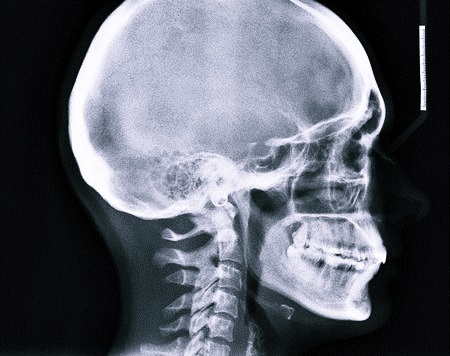

На пленке плотная ткань головы, к примеру, костная структура, имеет светлый (белый) оттенок, а мягкая ткань и воздушная полость – темный (черный). Диагностическое мероприятие показывает состояния, протекающие в следующих отделах:

Рентгенограмма черепа, костей данного отдела или основания позволяет выявить следующие состояния:

- трещины и перелом;

- симптомы остеосклероза и остеопороза;

- врожденные патологии костного аппарата.

В большинстве случаев для получения четкой картины состояния костей черепа используют прямую и боковую проекции. Первая позволяет оценить строение лицевого скелета, свода черепа, затылочного отдела и области шеи для обнаружения опухолей спинного мозга и других патологий. Рентген в боковой проекции назначают для определения состояния свода и основания черепа, шейных позвонков, лицевого скелета.